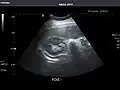

Liver: Diffusely homogeneous and normal in echogenicity. No focal mass or contour nodularity. No intrahepatic biliary ductal dilatation.

Liver -